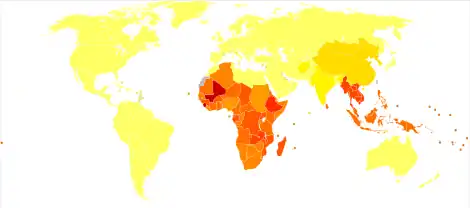

Epidemiology

It is estimated that between 576 and 740 million individuals are infected with hookworm.[58][26] Of these infected individuals, about 80 million are severely affected.[38] The major cause of hookworm infection is N. americanus which is found in the Americas, sub-Saharan Africa, and Asia.[15] A. duodenale is found in more scattered focal environments, namely Europe and the Mediterranean. Most infected individuals are concentrated in sub-Saharan Africa and East Asia/the Pacific Islands with each region having estimates of 198 million and 149 million infected individuals, respectively. Other affected regions include: South Asia (50 million), Latin America and the Caribbean (50 million), South Asia (59 million), Middle East/North Africa (10 million).[26] A majority of these infected individuals live in poverty-stricken areas with poor sanitation. Hookworm infection is most concentrated among the world's poorest who live on less than $2 a day.[15]

While hookworm infection may not directly lead to mortality, its effects on morbidity demand immediate attention. When considering disability-adjusted life years (DALYs), neglected tropical diseases, including hookworm infection, rank among diarrheal diseases, ischemic heart disease, malaria, and tuberculosis as one of the most important health problems of the developing world.[59][15]

It has been estimated that as many as 22.1 million DALYs have been lost due to hookworm infection. Recently, there has been increasing interest to address the public health concerns associated with hookworm infection. For example, the Bill & Melinda Gates Foundation recently donated US$34 million to fight Neglected Tropical Diseases including hookworm infection.[60] Former US President Clinton also announced a mega-commitment at the Clinton Global Initiative (CGI) 2008 Annual Meeting to de-worm 10 million children.[61]

Many of the numbers regarding the prevalence of hookworm infection are estimates as there is no international surveillance mechanism currently in place to determine prevalence and global distribution.[15]